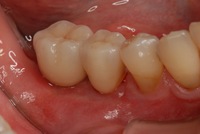

↑術後です。骨を増やす事でインプラントは埋入でき、そして機能させる事が可能となりました。

写真で見ると…

術前

![]()

術後![]()

この患者様は、全体の治療が終わるまで2年かかりました。一つの箇所だけで3回の手術(この方は、全体の治療で、9回の手術を行っています。)をされて、これに絶えられた患者様には、頭が下がります。